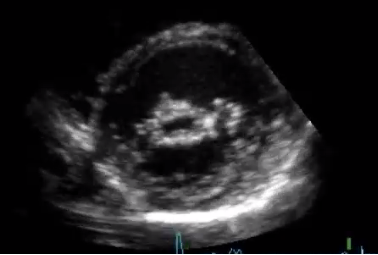

Johan inkommer med symptom och fysikaliska tecken på uttalad hjärtsvikt i form av läppcyanos, halsvenstas, ansträngningsdyspné, lungrassel, dämpning basalt över lungfälten, hepatomegali, dekliva pittingödem och sekundär mitralisinsufficiens. Inkompensationsbilden bekräftas med lungröntgen. QS-komplex sågs anteroseptalt och inferiort, vilket talar för genomgångna infarkter.

Ekokardiografi visar en uttalad nedsättning av vänsterkammarfunktionen orsakad av tidigare infarkter. En del av hjärtmuskeln apikalt har efter myokardnekros ersatts med ett bindvävsärr och blivit akinetisk, vilket innebär att den inte deltar i hjärtmuskelkontraktionen. Diagnosen hjärtsvikt bygger på förekomst av symtom och objektivt påvisad nedsättning av hjärtfunktionen.